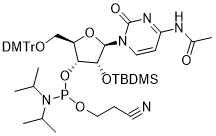

馬鞍山致研生物醫(yī)藥科技有限公司成立于馬鞍山市鄭浦港新區(qū)現(xiàn)代產(chǎn)業(yè)園。公司專(zhuān)注于生物小分子、醫(yī)藥中間體相關(guān)產(chǎn)品的研發(fā)和生產(chǎn),產(chǎn)品主要包括DNA亞磷酰胺單體、RNA亞磷酰胺單體、特殊單體以及按照客戶(hù)要求定制的RNA和DNA,并且公司提供定制合成等方面的研究服...

馬鞍山致研生物醫(yī)藥科技有限公司成立于馬鞍山市鄭浦港新區(qū)現(xiàn)代產(chǎn)業(yè)園。公司專(zhuān)注于生物小分子、醫(yī)藥中間體相關(guān)產(chǎn)品的研發(fā)和生產(chǎn),產(chǎn)品主要包括DNA亞磷酰胺單體、RNA亞磷酰胺單體、特殊單體以及按照客戶(hù)要求定制的RNA和DNA,并且公司提供定制合成等方面的研究服...